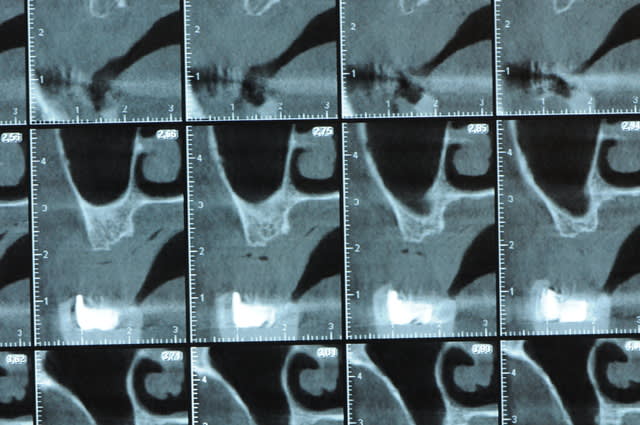

Une petite étude de ton cas D57

Les zones exploitables radiologiquement parlant:

Coupes implant

2,3 40100

4,96 35130 avec sinus lift mais difficile

5,25 35150

6,02 35130

6,78 35115 après réduction de hauteur de crête

7,26 35115 après réduction de hauteur de crête

8,51 35150

10,43 40115 ou 50115

11,10 40115

Ce qui nous fait 9 implants possible évidement avec un comblement de sinus on augmenterait encore les zones implantable mais ce n’est pas le but recherché, avec 8 (4+4) il doit être possible de faire une belle barre support de complet